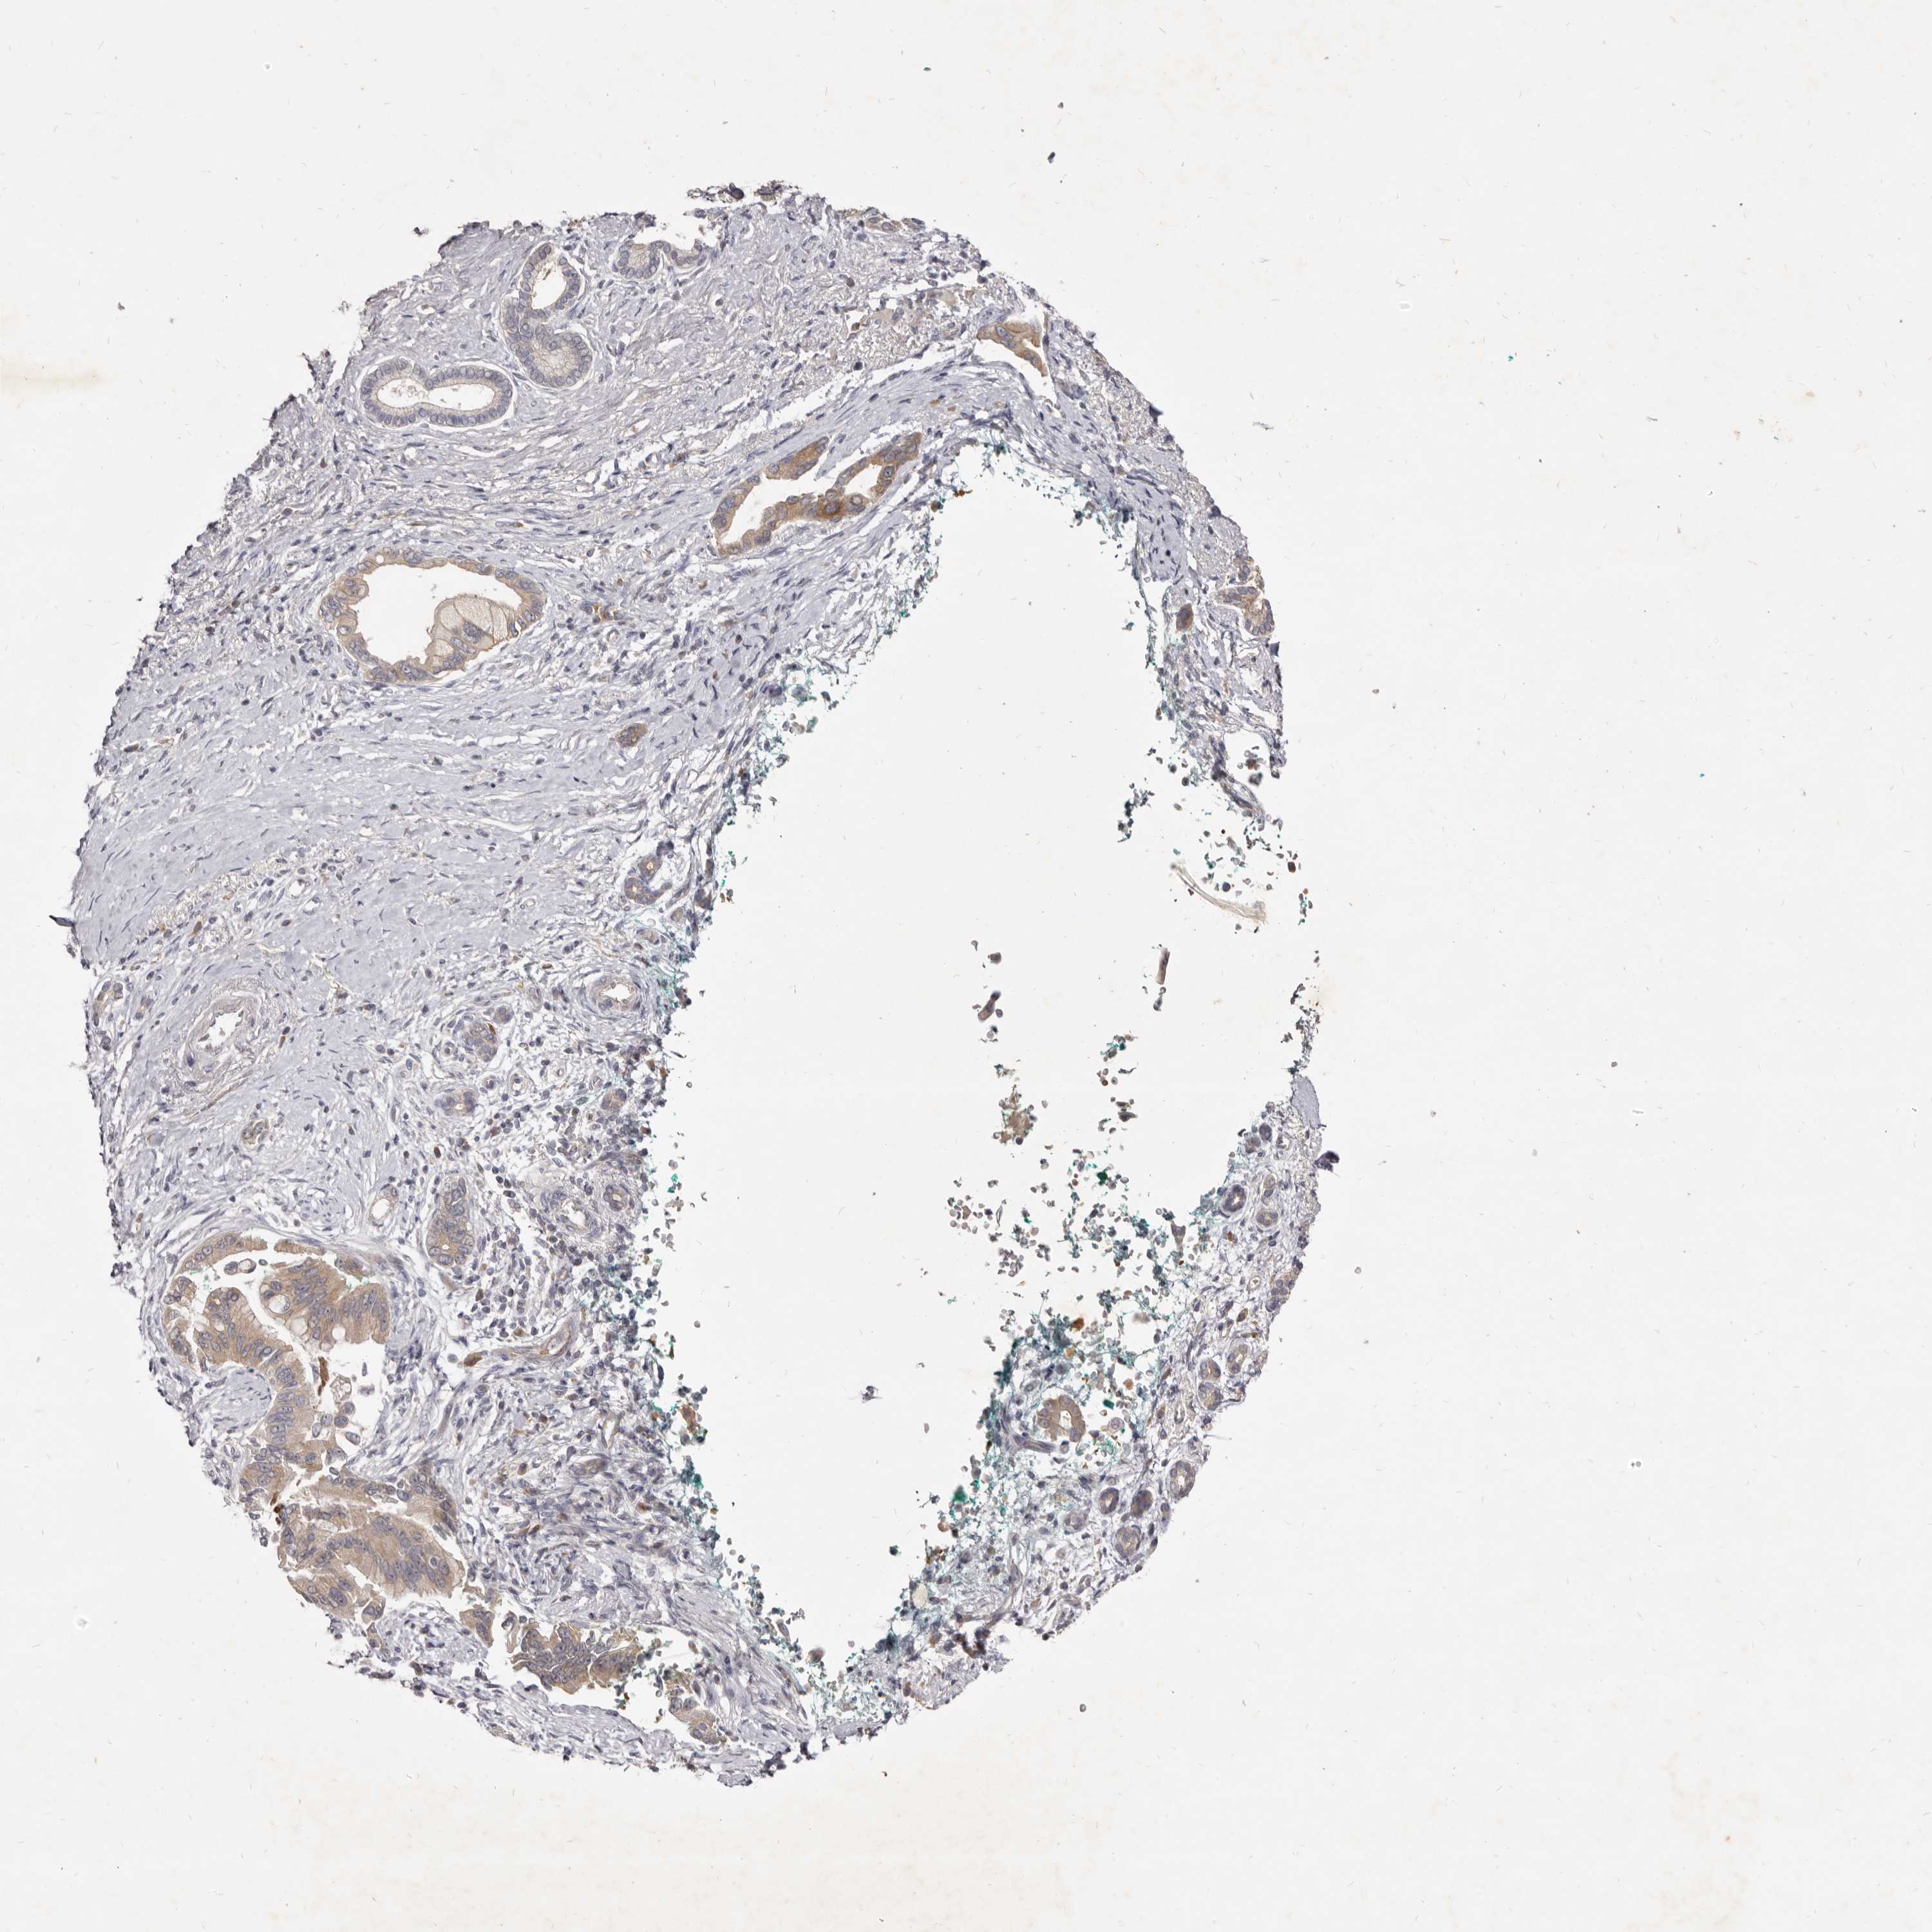

PANCREATIC CANCER - Protein expressioni

A mouse-over function shows sample information and annotation data. Click on an image to view it in a full screen mode. Samples can be filtered based on level of antibody staining by selecting one or several of the following categories: high, medium, low and not detected. The assay and annotation is described here.

Note that samples used for immunohistochemistry by the Human Protein Atlas do not correspond to samples in the TCGA dataset.

Antibody stainingi

Antibody staining in the annotated cell types in the current human tissue is reported as not detected, low, medium, or high, based on conventional immunohistochemistry profiling in selected tissues. This score is based on the combination of the staining intensity and fraction of stained cells.

Each image is clickable and will lead to virtual microscopy that enables deeper exploration of all samples and also displays staining intensity scores, fraction scores and subcellular localization as well as patient and tissue information for each sample.

Antibody HPA023081

Antibody HPA023103

Antibody HPA024795

Staining

High

Medium

Low

Not detected

Intensity

Strong

Moderate

Weak

Negative

Quantity

>75%

75%-25%

<25%

None

Location

Nuclear

Cytoplasmic/membranous

Cytoplasmic/membranous,nuclear

Adenocarcinoma, NOS